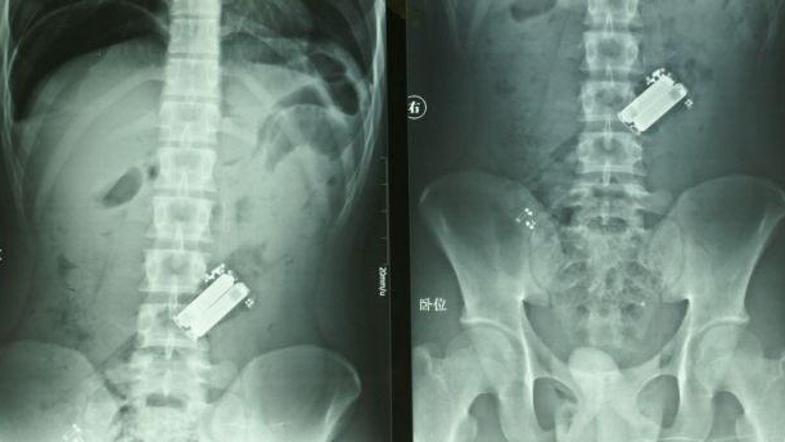

Daljinski upravljalnik v anusu

Huang Chen se je zbudil z daljinskim upravljalnikom v anusu. Žurnal24 main

Kitajcu Huangu Chenu priporočamo selitev. Po divji noči, v kateri se je mrtvo pijan zgrudil, so mu sostanovalci v zadnjico porinili daljinski upravljalnik. "Sprva nismo vedeli, kaj je v njegovem anusu. Bilo je nekaj krvi, daljinca pa ni omenjal. Ko smo videli rentgenske posnetke, nismo mogli verjeti svojim očem,“ je povedal zdravnik in dodal, da si bo mladenič kmalu opomogel, daljinskemu upravljalniku pa ni bilo pomoči.